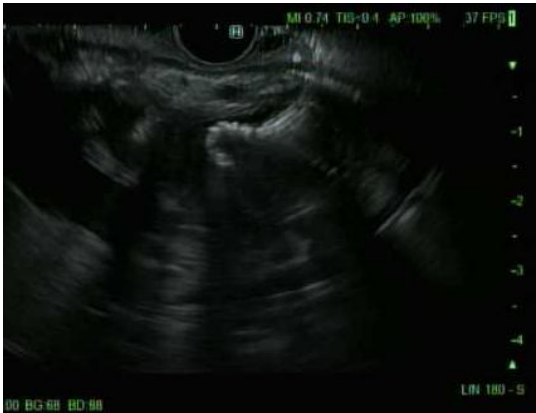

Figure 2. Endoscopic image showing an endoscopic ultrasound-guided LAMS deployed from the stomach to the gallbladder. Courtesy of Tony Brar, M.D.